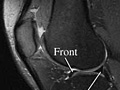

Magnetic Resonance Imaging (MRI) of the Knee

Magnetic Resonance Imaging (MRI) of the KneeSkip to the navigationTest OverviewMagnetic resonance imaging (MRI) is a test

done with a large machine that uses a magnetic field and pulses of radio wave

energy to make pictures of the knee. Muscles,

ligaments,

cartilage, and other joint structures are often best

seen with an MRI. In many cases MRI gives information about structures in the

body that cannot be seen as well with an